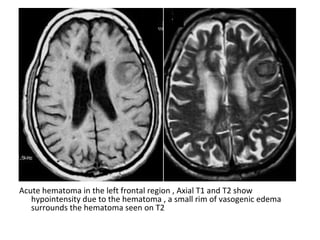

CT and T2W-gradient echo image of a hemorrhagic infarction

limited to the territory of the lateral lenticulostriate arteries